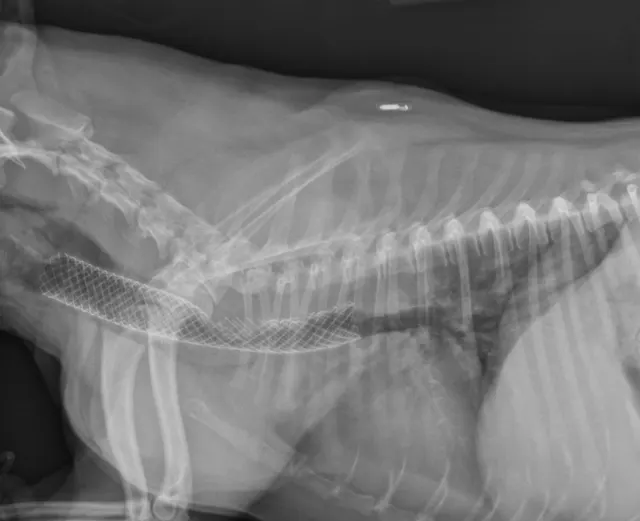

Many surgeons prefer intraluminal stents because they can be noninvasively placed in the cervical or thoracic trachea, reducing risk for complications and shortening anesthetic times. Vet Stent–Trachea is a woven, reconstrainable, self-expanding, nitinol stent3-8 (Figure 3). Nitinol, a nickel–titanium alloy, has thermal shape memory, super elasticity, and elastic hysteresis; the latter minimizes outward force on the interior lumen of the trachea, regardless of stent size.24 The undeployed intraluminal stent is secured within a low-profile delivery system that has radiopaque markers to facilitate positioning. As it is released from the catheter, the stent expands to meet the internal wall of the trachea, foreshortening as it increases in diameter. Because the stent is reconstrainable, it can be pulled back into the delivery system for repositioning after partial release.

Fully deployed stent. Courtesy of Infiniti Medical.

Partially deployed stent. Courtesy of Infiniti Medical.

The flexibility of woven nitinol stents allows them to maintain their cylindric shape along the length of the trachea, despite changes in tracheal direction or diameter. Radial stress applied to the interior lumen of the trachea prevents migration of the stent, as long as an appropriate size is chosen.2,26